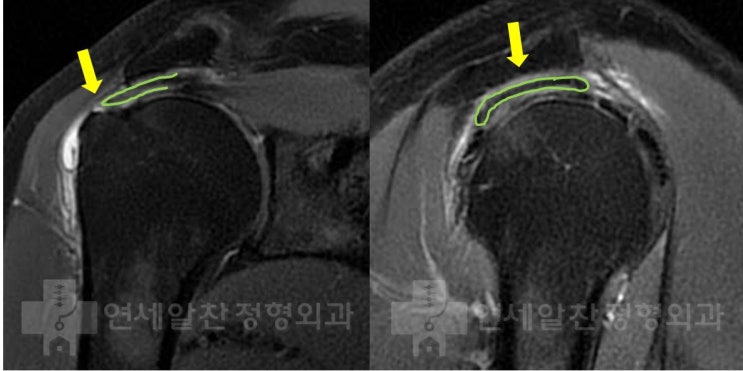

극상근 점액낭측 파열에서 이중교량형 봉합법을 이용한 수술의 결과

58세 여자환자로 3개월전 일하는 도중 발생한 어깨 통증을 주소로 본원으로 내원하였다. 타원에서 주사치료...

고령의 극상근 파열에서 이중교량형 봉합법을 이용한 수술의 결과

73세 여자 환자로 약 2년간의 우측 어깨 통증을 주소로 본원으로 내원하였다. 타병원에서 수차례 주사치료,...

극상근 점액낭측 파열에서 이중 교량형 봉합술의 결과

44세 남자환자로 다이빙 하면서 수상을 당한 후 발생한 우측 어깨 통증을 주소로 내원하였다. 이학적 검사...